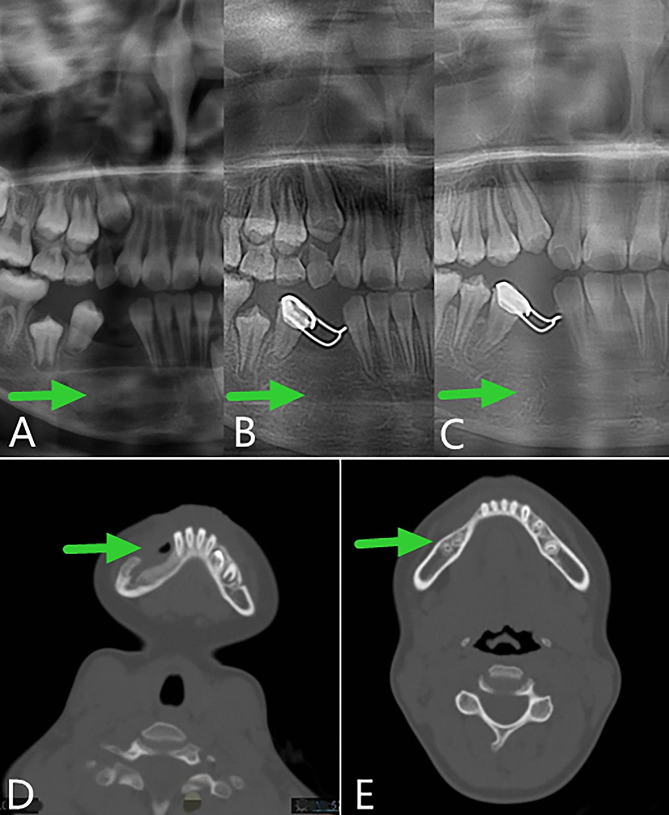

The right mandibular body was slightly distended, the mouth opening was normal, and there was no numbness in the lower lip. Mixed dentition was found in the mouth, vestibular sulcus was distended from 42 distal to 46 mesial in the right mandible, and a palpable mass of about 2 × 3 cm was observed. The preoperative panoramic radiography was shown in Fig. 6, indicating that the tumor was cystic, with a notch-like bony alba line on the edge. The boundary was clear, the lower part was adjacent to the lower edge of the mandible, the tooth germ of tooth 43 was seen inside, and the teeth on both sides of the tumor were squeezed and displaced. The preoperative diagnosis was AM of the right mandible.

Fig. 6.

Preoperative panoramic radiography

About 1 week after the operation, the iodoform gauze was removed from the patient in the outpatient clinic, and a plug device was made and installed in the prosthetic department. After that, the reexamination was carried out at the outpatient clinic regularly. During the reexamination, the main focus was on whether there was any abnormality in the soft and hard tissues of the operation area. The plug device was adjusted, and panoramic oral radiographs were taken to evaluate the shrinkage of the cyst. Figure 7 showed that the cyst cavity was significantly reduced during the follow-up visit, and a considerable amount of bone formed at 4 months after the operation.

Fig. 7.

Postoperative panoramic oral radiogram. A, 1 week. B, 2 months. C, 4 months

After evaluation by our team, the child underwent stage II surgery in our hospital 4 months after the first operation (2019-08-01) to close the window, and the lesion was further clarified. During the operation, we found that the bone cavity in the opening window became shallow and narrow. The incision was made along the edge of the opening window, and the mucosa of the bony cavity and the surface part of the oral mucosa were excised together. The mucoperiosteal flaps on both sides were released, and the opening window was closed and sutured. The postoperative paraffin-embedded section indicated hyperplastic fibers and mucosal epithelium, and a small amount of reticular hyperplasia of the squamous epithelium was observed focally (Fig. 2D). Combined with the medical history, AM was not excluded. The child was followed up for 28 months after surgery (28 months after curettage and fenestration and 24 months after secondary curettage and fenestration closure). The operation area continued to have good osteogenic remodeling, and the bone appearance was improved without recurrence (Fig. 8).

Fig. 8.

Panoramic radiography and computed tomography. A, B and C, Panoramic oral radiogram showing 2 months, 1 year and 2 years respectively after secondary curettage and fenestration closure. D and E, Computed tomography view displaying 4 months and 28 months after the curettage and fenestration